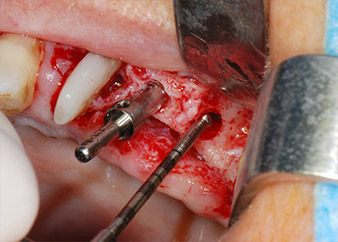

One month later, on the day of surgery, pain and inflammation at tooth 24 were minimal, but mobility of Miller class 2 was still present. After opening the flaps and cleaning the periapical and peri radicular infected tissue, the extent of the bone defect became obvious (Figs. 2 and 3).

Fig. 2 and 3: After raising flaps, one month after endodontic revision and initiation of full-mouth periodontal therapy, the buccal root of tooth 24 showed a total loss of bone and attachment.

However, we maintained our initial plan to retain both teeth as temporary bridge abutments during the six-months osseointegration period of the implants. At reentry, the situation would have to be reassessed. First, in an attempt to manage the endo-perio problem, the remaining root surface was carefully debrided with piezoelectric equipment (Piezomed, W&H, used with the spatula-shaped insert S1, originally designed for erosion of the lateral sinus wall) (Fig. 4).